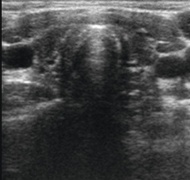

Basisuntersuchung ist der Ultraschall (Sonografie), um Größe und Struktur des Organs zu erfassen (Abbildung 2). Knoten werden nach Aufbau, Struktur und Abgrenzbarkeit beurteilt und die Größe für weitere Verlaufskontrollen dokumentiert (Abbildung 3).

Neben der operativen Entfernung der Schilddrüse ist die häufigste Ursache eine chronische, immunologisch bedingte Entzündung, die Autoimmunthyreoiditis Hashimoto. Hierbei führt eine entzündliche Infiltration des Organs durch Lymphozyten zu einer progredienten Zerstörung der Schilddrüsenzellen. Beweisend sind Antikörper gegen die Thyreoideale Peroxidase (TPO) im Blut; dieses Enzym ist für die Hormonsynthese erforderlich. Häufig resultiert eine Atrophie der Schilddrüse, die sich im Ultraschall klein und typisch echoarm darstellt (Abbildung 8).